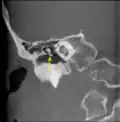

CT image of malleus- Auditory ossicles. Tympanic cavity. Deep dissection.